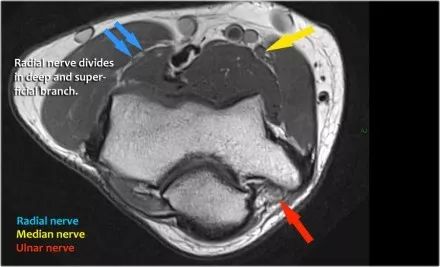

桡神经:在桡骨头水平可以最好地识别桡神经,在那里你可以看到桡骨隧道中的浅表和深支(箭头)。这是寻找桡神经的非常一致的地方。

深分支形成后骨间神经,穿过Frohse拱门(箭头)的旋后肌。